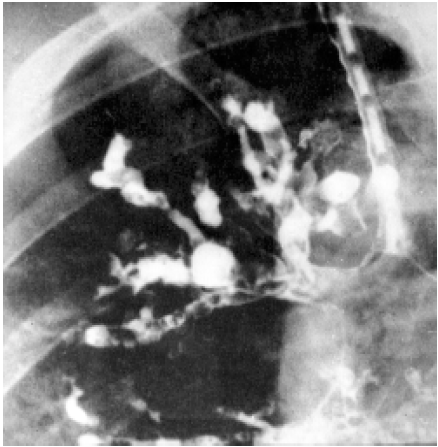

1. Radiografía de tórax